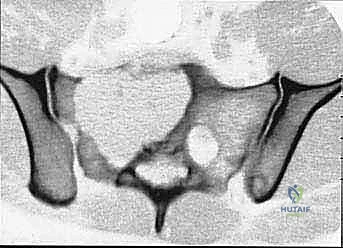

* CT with Intravenous Contrast and 3D Reconstruction (FIG 3): This is our workhorse for assessing bone involvement, destruction, and the critical relationship between the tumor and major pelvic blood vessels. It reveals any distortion of the pelvic anatomy and guides resectability. Figure 3A clearly shows extensive bone destruction and tumor extension into the pelvis and gluteal region. Figure 3C highlights an extensive tumor on the medial aspect of the ilium with destruction of the inner table.